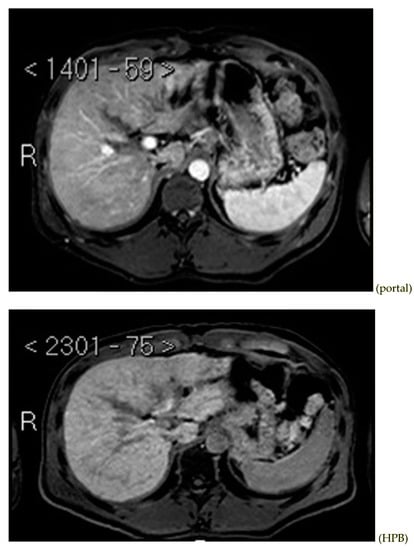

Subsequently, an upper-abdomen Computed Tomography (CT) scan and liver Magnetic Resonance Imaging (MRI) were performed (Figure 1, Figure 2, Figure 3, Figure 4, Figure 5, Figure 6 and Figure 7).

Figure 5.

MRI T2.

Figure 6.

MRI arterial, portal, and HPB phases.

A mass of 1.8 cm was detected within the biliary branch for the third hepatic segment, characterized by nodular impregnation in the arterial phase and irregular and partial washout in the portal venous phase. These findings were compatible with a heterologous lesion, although it was not possible to perform a diagnosis among HCC, intrahepatic CCA or other pathological lesions.